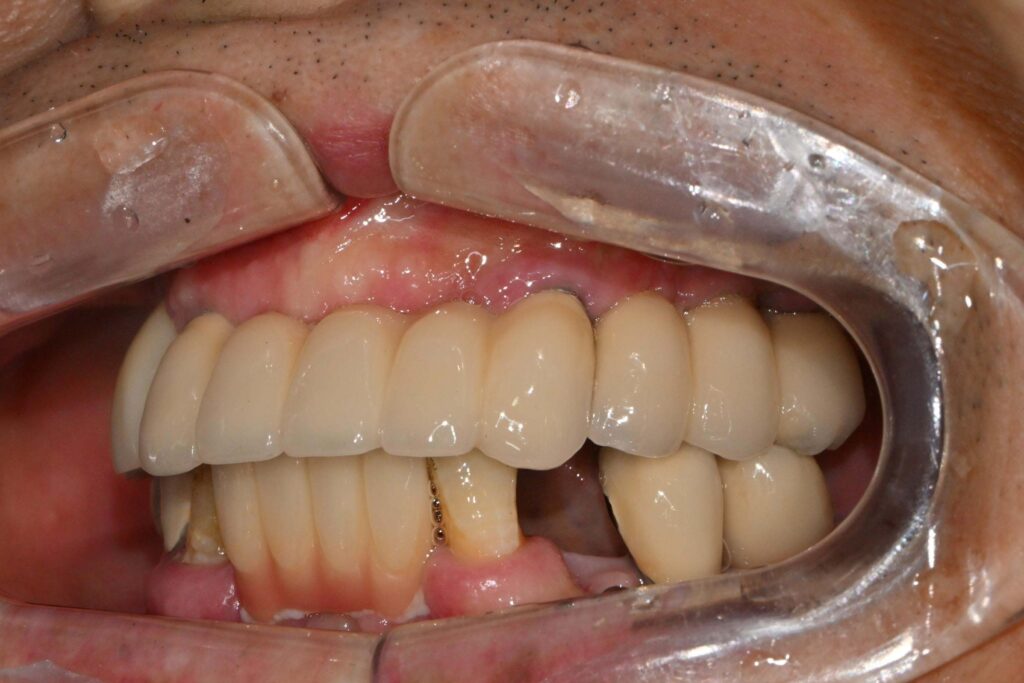

이후 잇몸이 회복되면 제작할 보철의

색을 고릅니다.

자연스러운 색으로 제작하여야,

보철을 올렸을 때도

어색한 느낌 없이 조화로워 보입니다.

최종 보철을 제작하기 전까지

임시 치아를 올려 심미성과

저작 기능을 잃지 않도록 합니다.